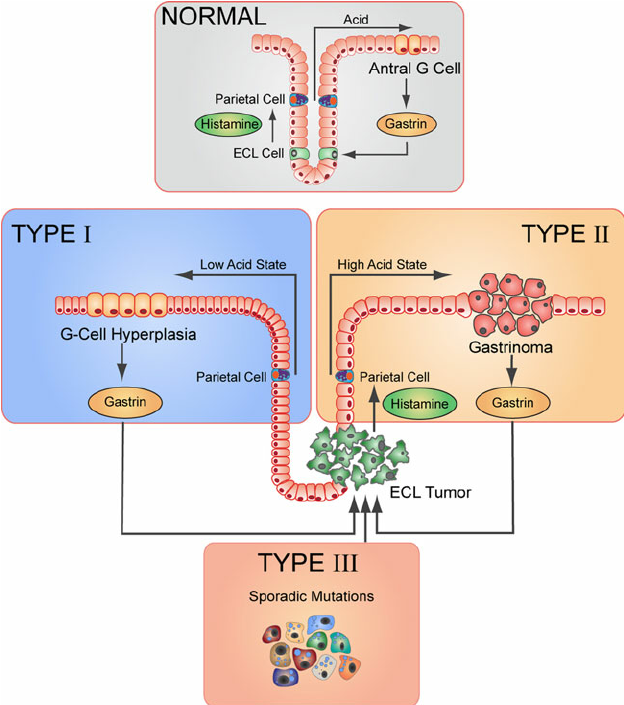

Vad vill denna grekiska bild förmedla?

- ECL:om typ 1 uppstår sekundärt till hypergastrinemi beroende på ex atrofisk gastrit, kan tas bort ganska enkelt och metastaserar sällan

- ECL:om typ 2 - associerade med Zollinger-Ellisons syndrom (gastrinproducerande tumör sm förekommer som delmanifestation vid MEN1) - behandlas som ovan)

- ECL:om typ 3 - sporadisk

Dessa kan producera histamin